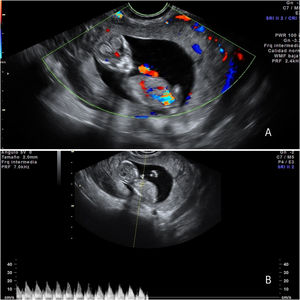

La ecografía transvaginal y abdominal mostró un útero regular con endometrio homogéneo, DIU normoinserto y ausencia de gestación intrauterina. En el área anexial derecha se observó un saco gestacional de 8cm que parecía localizarse en ovario derecho, con embrión con CRL acorde a 12+4 semanas con actividad cardiaca presente (figs. 1 y 2). No se conseguía visualizar el anejo izquierdo debido al tamaño de la gestación. Había líquido libre en Douglas en cantidad escasa. La analítica resultó sin hallazgos.

Imágenes de ecografía transvaginal y transabdominal en las que se observa un corte longitudinal A) y transversal B) del útero con DIU normoinserto y ausencia de gestación intrauterina, y una masa ovárica derecha C) compatible con embarazo ectópico ovárico con gestación evolutiva D). El examen en tiempo real mostró que el saco gestacional y el ovario no se podían separar al mover la sonda transvaginal, lo que era diagnóstico de embarazo ectópico intraovárico.